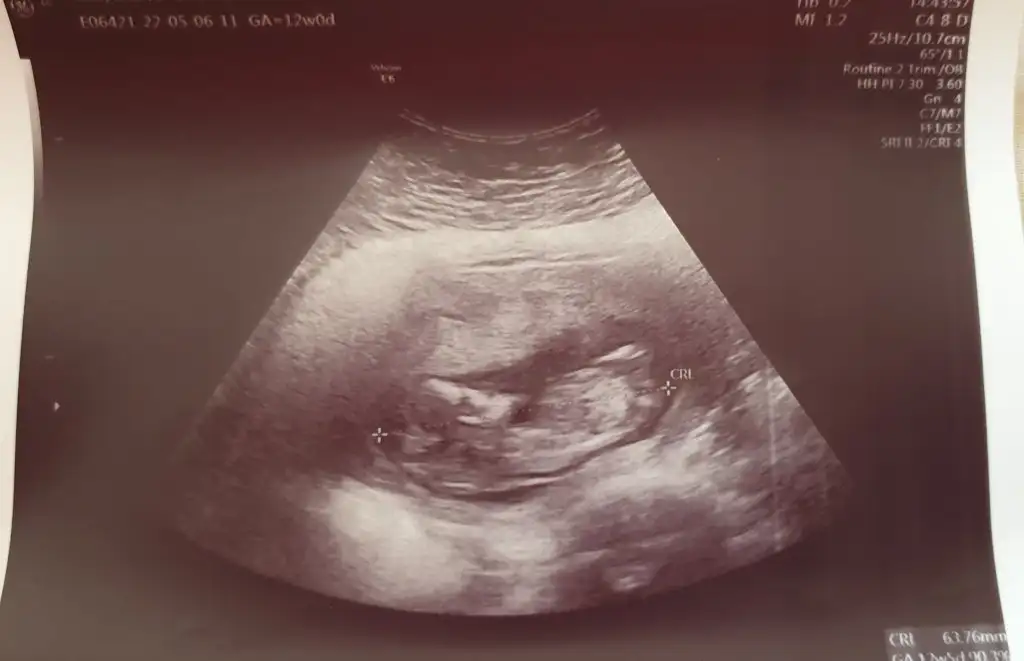

Merhaba Pasha22 Pasha22 acaba bana da yorum yapabilir misiniz? Merakla bekliyorum cinsiyeti.

Ilk foto 13+4

2.foto 11+5

3.foto 6+3

Hepsi karından.